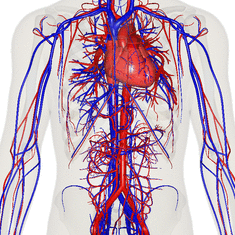

![]() The human circulatory system (simplified). Red indicates oxygenated blood carried in arteries. Blue indicates deoxygenated blood carried in veins. Capillaries, which join the arteries and veins, and the lymphatic vessels are not shown. | |

The circulatory system, also called the cardiovascular system or the vascular system, is an organ system that permits blood to circulate and transport nutrients (such as amino acids and electrolytes), oxygen, carbon dioxide, hormones, and blood cells to and from the cells in the body to provide nourishment and help in fighting diseases, stabilize temperature and pH, and maintain homeostasis.

The circulatory system of the blood is seen as having two components, a systemic circulation and a pulmonary circulation.[4]

The essential components of the human cardiovascular system are the heart, blood and blood vessels.[6] It includes the pulmonary circulation, a "loop" through the lungs where blood is oxygenated; and the systemic circulation, a "loop" through the rest of the body to provide oxygenated blood. The systemic circulation can also be seen to function in two parts – a macrocirculation and a microcirculation. An average adult contains five to six quarts (roughly 4.7 to 5.7 liters) of blood, accounting for approximately 7% of their total body weight.[7] Blood consists of plasma, red blood cells, white blood cells, and platelets. Also, the digestive system works with the circulatory system to provide the nutrients the system needs to keep the heart pumping.[8]